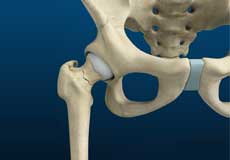

Hip Joint

The hip joint is the largest weight-bearing joint in the human body. It is also referred to as a ball and socket joint and is surrounded by muscles, ligaments, and tendons. The thigh bone or femur and the pelvis join to form the hip joint.

Bones and Joints

The hip joint is the junction where the hip joins the leg to the trunk of the body. It is comprised of two bones: the thigh bone or femur and the pelvis which is made up of three bones called ilium, ischium, and pubis. The ball of the hip joint is made by the femoral head while the socket is formed by the acetabulum. The Acetabulum is a deep, circular socket formed on the outer edge of the pelvis by the union of three bones: ilium, ischium, and pubis. The lower part of the ilium is attached by the pubis while the ischium is considerably behind the pubis. The stability of the hip is provided by the joint capsule or acetabulum and the muscles and ligaments which surround and support the hip joint.